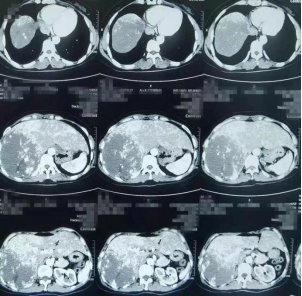

张女士的术前CT片子

今年41岁的张女士(化姓)在半年前的体检中发现了肝脏右部有一个血管瘤,但由于疫情,加上肿瘤是良性的,身体没有任何不适,所以她选择择期手术。一周前,张女士总是感觉腹胀,她才想起来到医院复查。检查结果令人大吃一惊,半年时间血管瘤直径已达20厘米,右半肝几乎全部被肿瘤占据,压迫到了周围器官,需要立即手术。